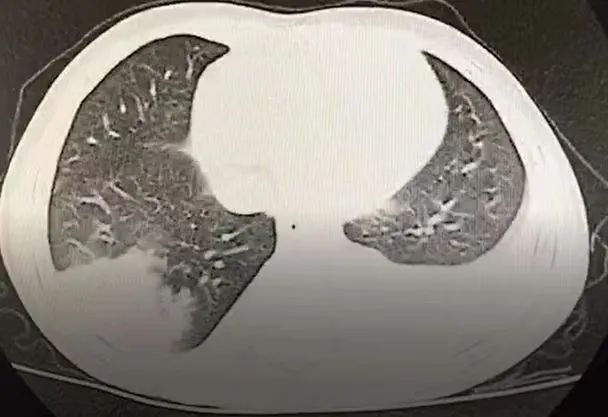

为什么聪聪这么容易出现感染呢?其背后的原因是什么?经常感染,反复而且多部位的感染引起了肾脏免疫科医生的警觉,判断聪聪极有可能存在免疫性缺陷问题。立即进行免疫功能检查,果然孩子的免疫球蛋白极为低下,血清IgG 0.236 g/L、IgA0.067 g/L、IgM 0.042 g/L(正常年龄孩子为6.6 -10.39 g/L、0.58-1.02 g/L、1.1-1.8 g/L),远低于年龄正常值。聪聪患有的是一种罕见的先天性免疫缺陷病——X连锁无丙种球蛋白血症。

找清楚病因,团队为患儿进行了对症治疗,目前通过定期输注免疫球蛋白等替代治疗,聪聪身体抵抗力明显增强,终于不再经常生病、输液,可以像其他孩子一样正常生活了。